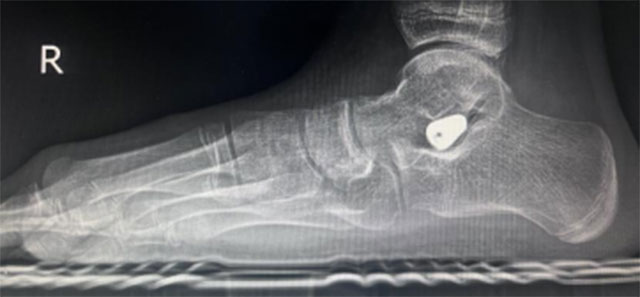

2024年6月13日,西南医科大学附属中医医院骨伤科关节·足踝组张磊博士门诊接诊了一名扁平足的初中生。14岁的小莉走路过程中足底有疼痛感,长时间走路后会感觉足底肿胀,遂来医院就诊,被诊断为“右足副舟骨痛+右足扁平足”,张磊博士团队考虑小莉实际情况,经微创治疗距下关节制动术后,小莉疼痛症状缓解。

12月1日,小莉再次来到骨伤科关节·足踝组复查,外观可见扁平足改善效果明显。

部分青少年患者可选择放入距下关节制动器,改善距下关节活动,缓解疼痛,一定程度改善足的外观及畸形。可联合进行副舟骨切除和胫后肌腱止点重建术。